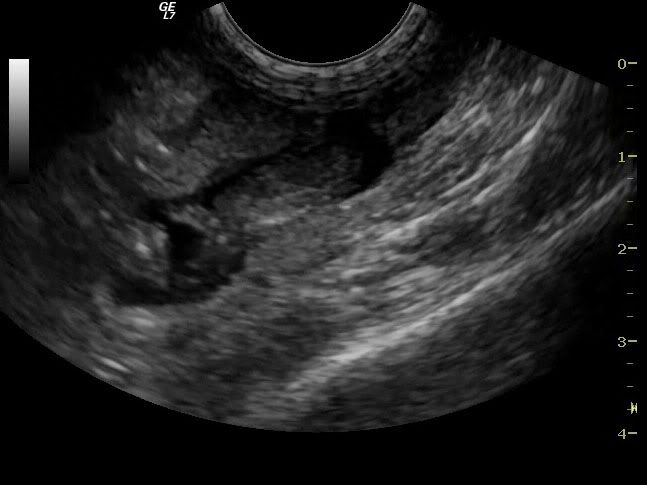

Her er en lille hvalp :D

og endnu en :D